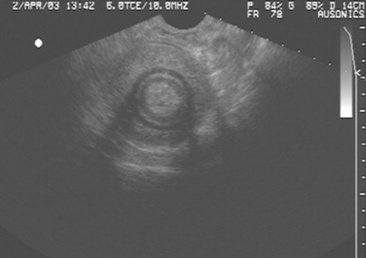

Ultrasound evaluation of horses with abdominal pain (colic) provides a rapid method to identify abnormalities within the gastrointestinal tract. Distention of the small intestine to a diameter greater than 5 cm has been strongly associated with strangulating or obstructing lesions19 (Fig. 32-11). In foals with intussusception, the small intestine appears enlarged and there is generally distended small intestine orad to the lesion; however, at the site of the intussusception there is a normal-appearing small intestinal wall (intussuscipiens) surrounded by a larger structure that appears to surround the inner small intestinal wall (called the intussusceptum)19 (Fig. 32-12). Large colon torsion occurs when the large colon rotates 360 degrees or more around the root of the mesentery to cause occlusion of venous drainage while maintaining arterial flow. This causes the wall to become thick and edematous. If ultrasound is performed in the cranioventral abdomen, just caudal to the xiphoid process, then a colon wall size greater than 9 mm is 100% specific for a large colon torsion21 (Fig. 32-13). A large colon displacement would have minimal to no vascular compromise, so it would be an ultrasound diagnosis based on exclusion. Chronic displacements did have a mild amount of edema in the colon wall, causing the size to be approximately 7 mm thick but never greater than 9 mm in the one study described.21 The colon and small intestinal wall will also become thick with inflammation. Small intestinal wall thickness greater than 4 mm is indicative of inflammation.19 The right dorsal colon can be imaged in the right tenth to twelfth intercostal space around the region of the costochondral junction, and a focal wall thickness of 9 to 12 mm has been identified with right dorsal colitis.23

image

Fig. 32-11 Transabdominal ultrasonographic image of a 6-year-old thoroughbred gelding with acute onset of colic. The small intestine is 7 cm in diameter and was noted to have minimal to no contractility. This is consistent for mechanical ileus. A strangulating lipoma was identified at surgery.

Courtesy of Cornell University.